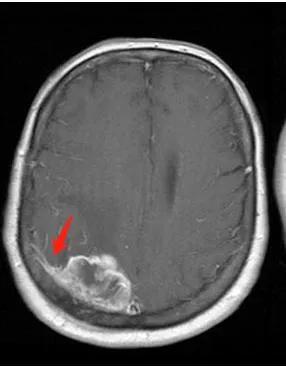

一位50岁的女性患者因持续头痛和视力模糊就诊。经过MRI检查,医生发现她大脑右侧有一个直径约3厘米的肿瘤。这个案例揭示了一种常见的脑部疾病——脑膜瘤。

诊断脑膜瘤主要依靠神经系统检查和影像学检查。CT扫描和MRI扫描是常用的诊断工具。有时,可能需要进行活检以排除其他类型的肿瘤,并确认脑膜瘤的诊断结果。